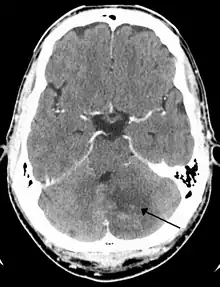

The three major arteries of the cerebellum: the SCA, AICA, and PICA | |